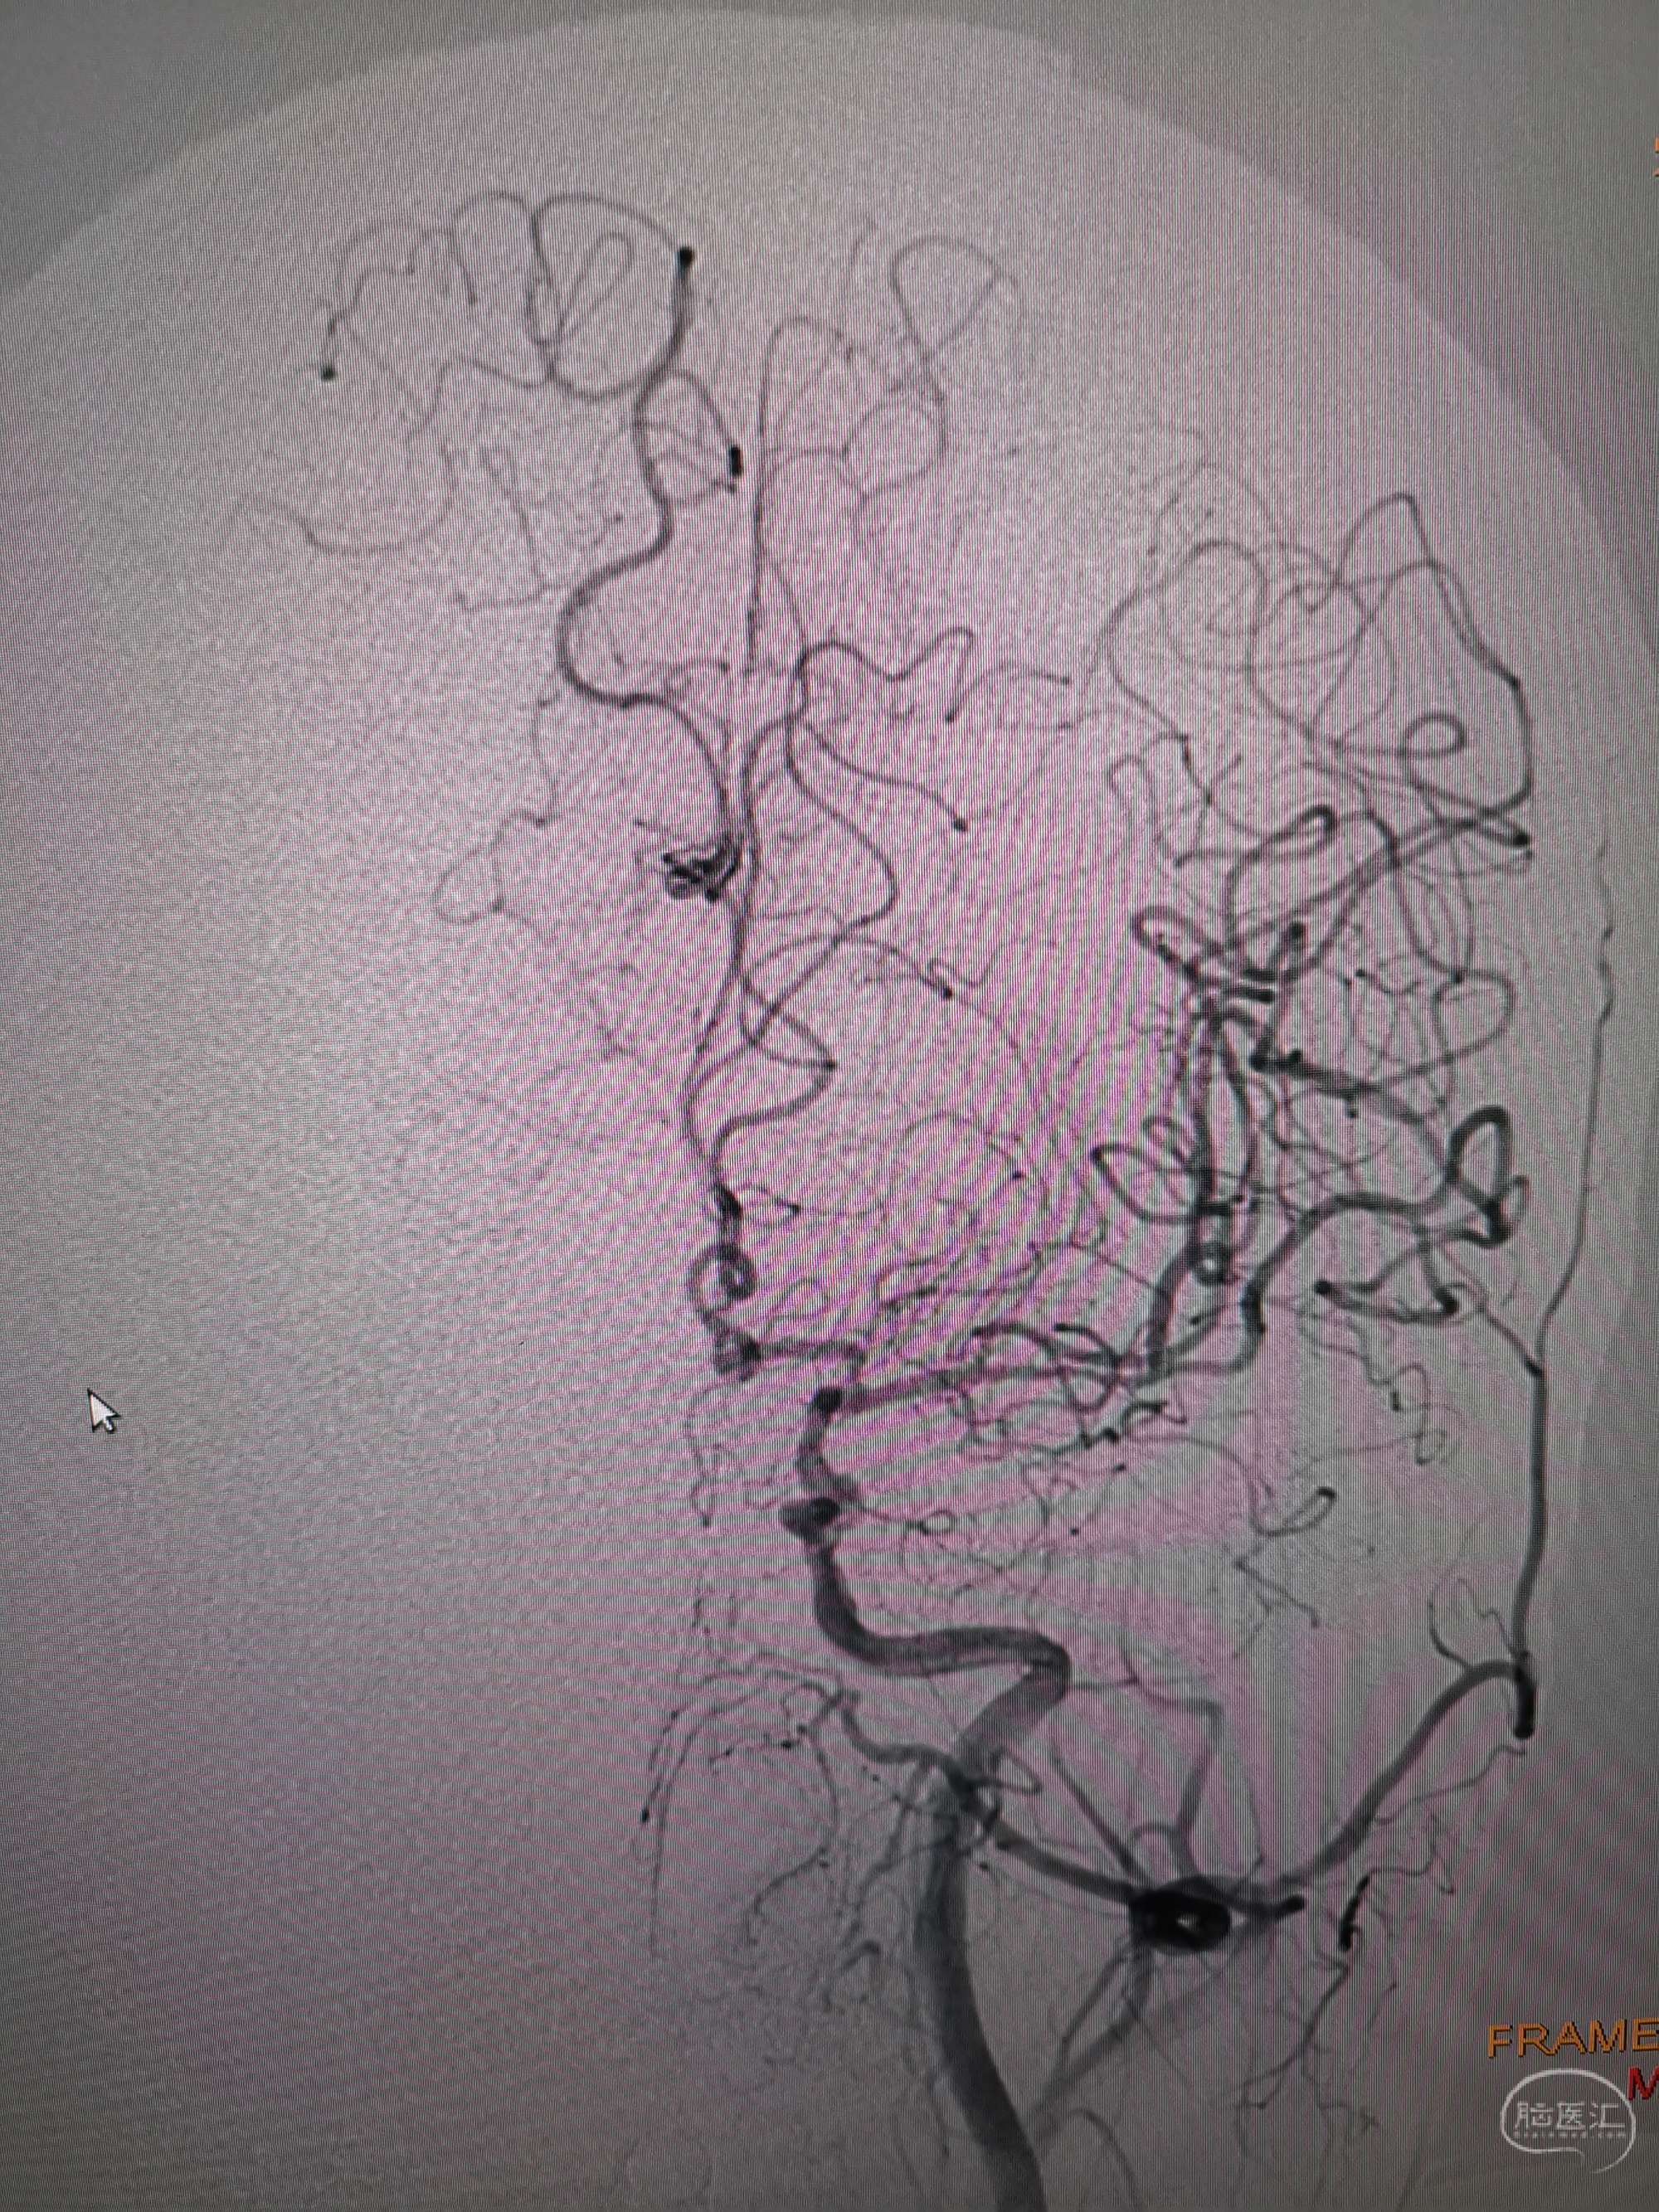

入院造影影像

术前再次造影评估

右侧椎动脉穿支供血及左侧PICA供血较入院时略有改善,但改善不明显。故按计划行左侧椎动脉再通术